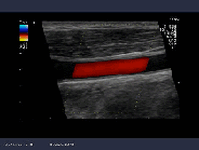

頚動脈エコー

超音波検査装置 (HITACHI ARIETTA 60)

超音波を使って頚動脈の状態を調べる検査です.血管の壁の厚さ(サビのつき具合)を測定し動脈硬化の程度を判定します.頚動脈の行き着く先は

『脳』です.すなわち頚動脈の動脈硬化性病変は脳梗塞の大きなリスクになるのです.頚動脈の動脈硬化の程度は全身の動脈硬化の進行具合の指標に

もなります.また,高血圧,糖尿病,高脂血症とも密接に関連し,治療の良否の判断にも利用されます.検査に要する時間は,10~20分位で,

特に予約は必要ありません.痛みや危険性は全くない安全な検査です.

●保険適応の検査であり,費用は3割負担の方で,1650円,1割負担の方ですと550円位です.